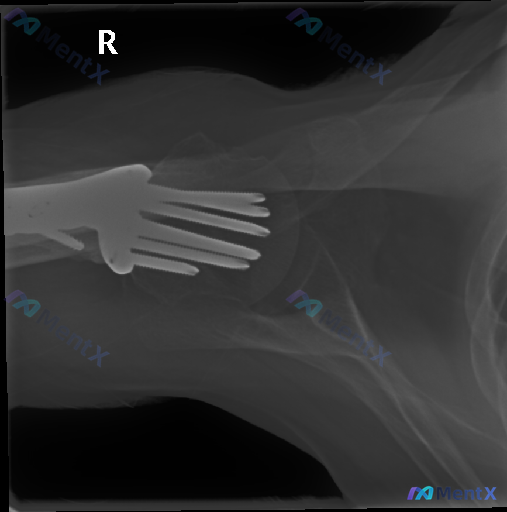

整理到一张左侧肩关节及肱骨的X光片资料,情况如下: 影像显示的是左侧肩关节及上臂全长,投照体位并非标准的肩关节“Y”位,而是一张包含肩关节、肱骨全长同时也显影了肘关节的侧位或斜向投影。 能看到肱骨近端有明显的金属内固定物(解剖型锁定钢板及多枚螺钉),钢板在肱骨外侧。不过因为金属内固定的存在,局部骨骼...

整理到一张右肩的术后斜位(Scapular Y-view)片,第一眼感觉还不错: - 投照体位标准,Y字结构清晰 - 肱骨近端骨折术后,钢板螺钉在位 - 肱骨头在关节盂中心,没脱位 - 软组织也没明显肿胀或巨大钙化 但结合后续的分析报告来看,这张片里其实藏着不少需要警惕的隐性/潜在异常风险,优先级甚...